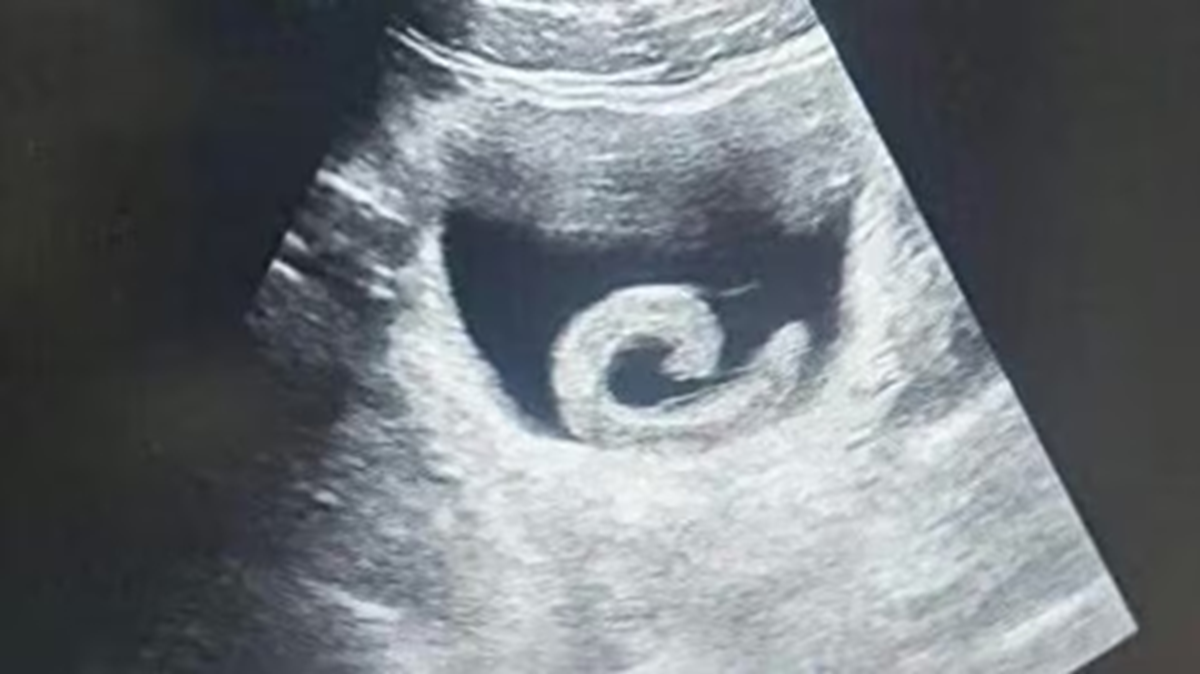

Hình ảnh siêu âm cho thấy một con đỉa sống trongbàng quang của người đàn ông ở Trịnh Châu, Trung Quốc, trước khi được các bác sĩ tiến hành phẫu thuật lấy ra. Ảnh: O.C.

Trước khi vào viện cấp cứu Zheng đã phải chịu cơn đau dữ dội đến mức không đi nổi. Khi nghe lý do, các bác sĩ không khỏi sửng sốt. Kết quả siêu âm xác nhận đúng như anh trình bày: một con đỉa sống đang ở trong bàng quang. Ngay lập tức, các bác sĩ chuẩn bị cho ca phẫu thuật khẩn cấp nhằm loại bỏ ký sinh trùng và cứu mạng bệnh nhân.